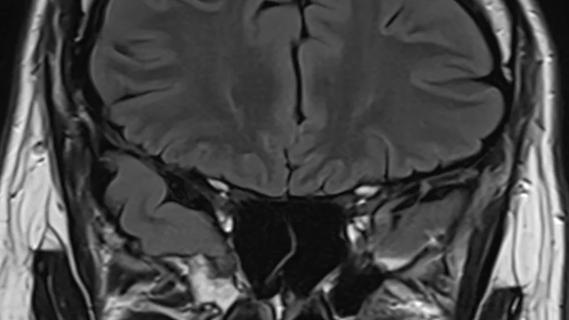

MRI of the brain against black background

Advanced Neuroimaging and Clinical Perseverance Make Sense of a 68-Year-Old’s Progressive Symptoms

A case study in pairing imaging acumen with subspecialty expertise to yield answers and symptom relief